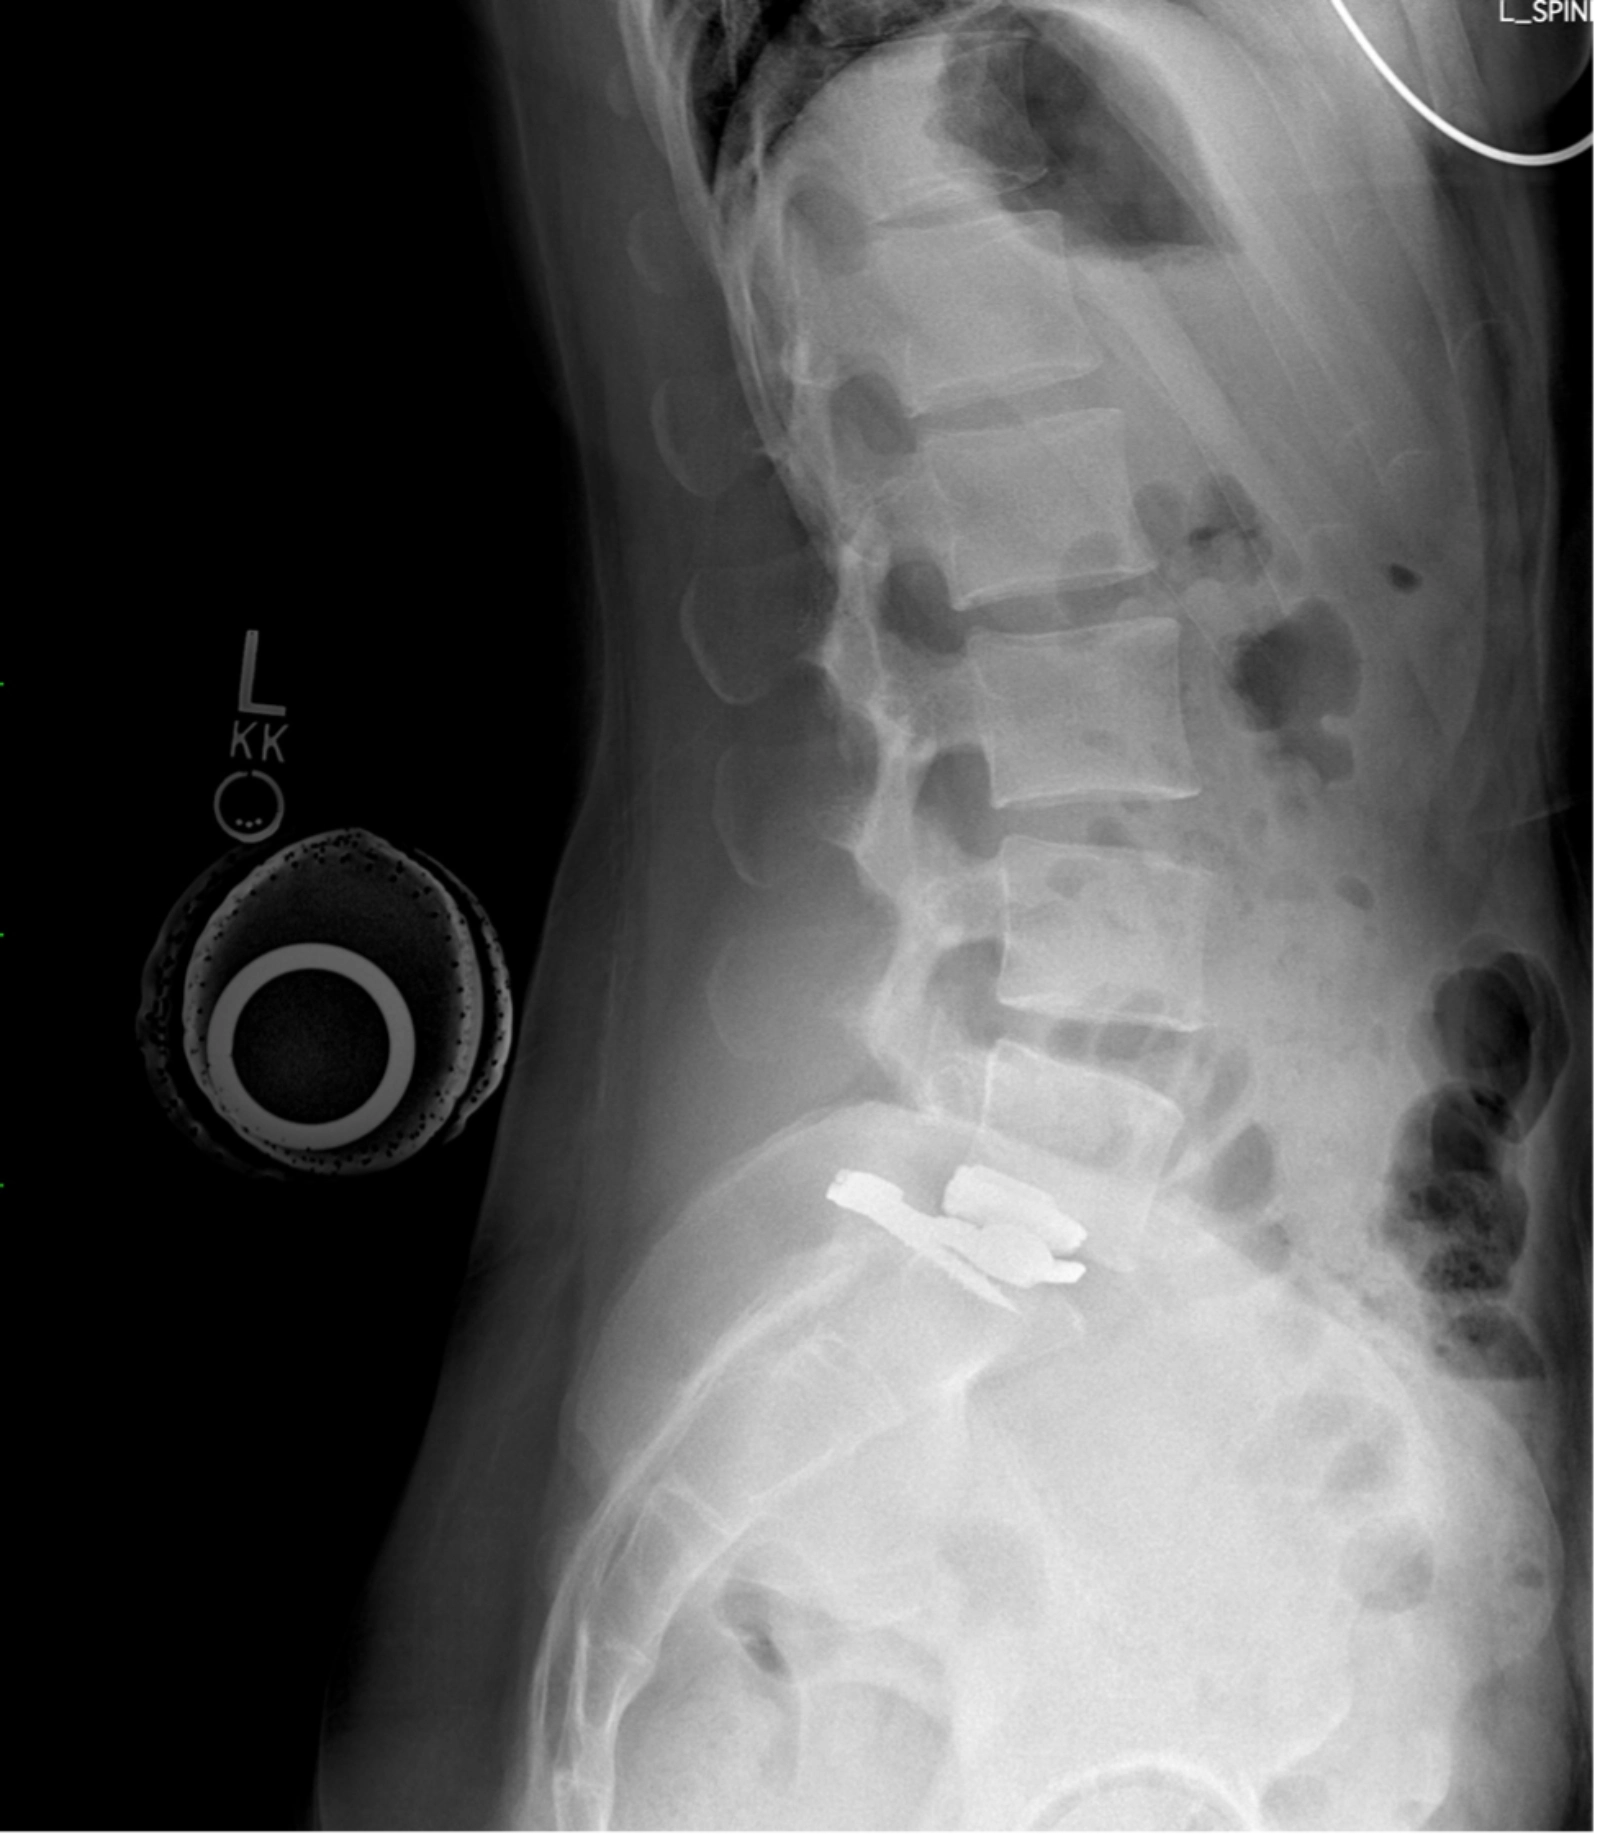

Lumbar Total Joint Replacement (MOTUS) is an innovative, first-of-its-kind total joint replacement for the lumbar (lower) spine that replaces both the intervertebral disc and the facet joints in a single motion-preserving procedure.

Unlike traditional spinal fusion, which permanently locks two vertebrae together, MOTUS is designed to restore natural motion and balance by reconstructing the entire joint unit of the spine. This emerging technology aims to provide comprehensive stability and motion in patients with degenerative lumbar conditions that have historically required fusion surgery.

The Lumbar Total Joint Replacement MOTUS procedure is performed through a posterior approach (through the back), allowing direct access to the affected spinal segment.

During the procedure:

- The surgeon accesses the spine from the back

- Both damaged facet joints are removed

- The diseased spinal disc is removed

- The MOTUS implants are positioned bi-laterally to replace the entire joint

Once the implants are placed, its dual bearing components are designed to mimic the natural mechanics of the spine. This allows the implant to resist rotation and shear forces while supporting axial loads, similar to how a healthy disc and facet joints function together.